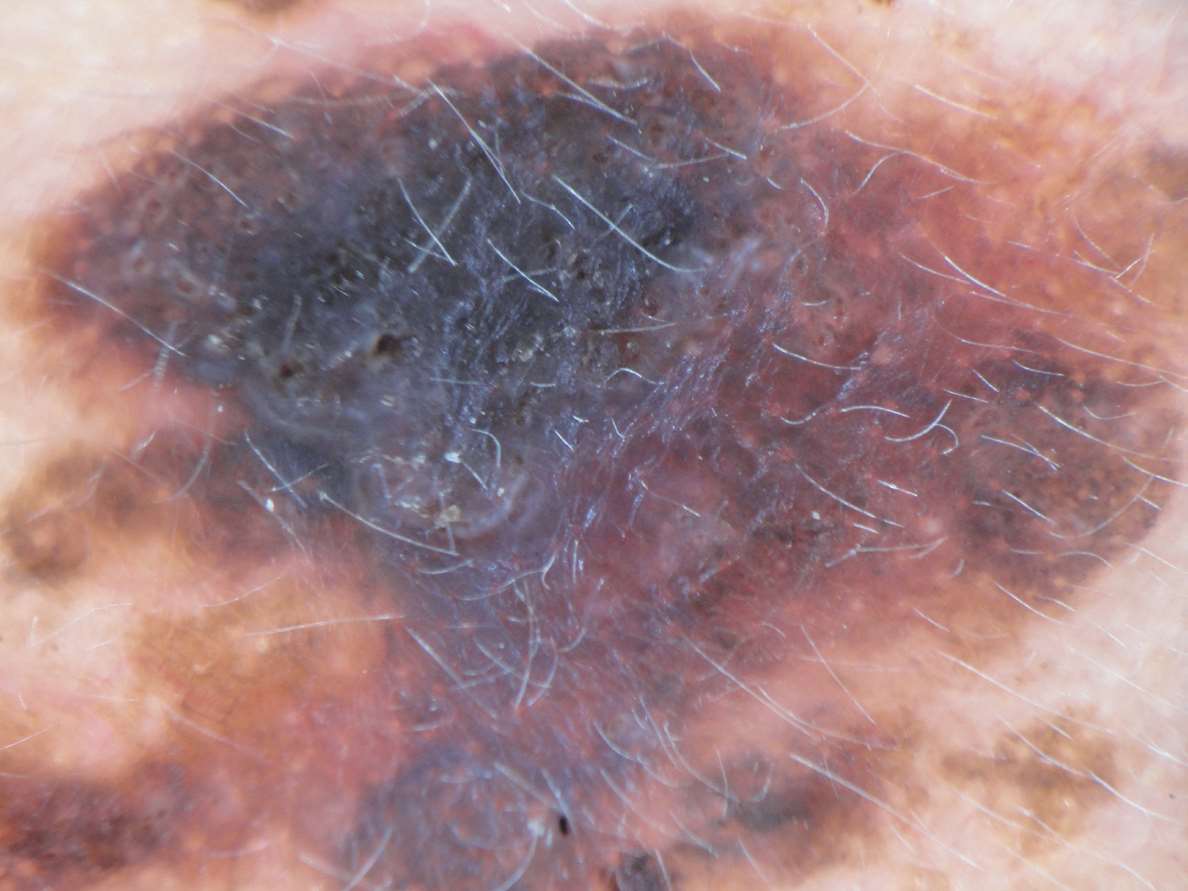

大斑点(blotches)又称色素加深的无结构区,指局限或弥漫性分布的色素遮盖其下的组织结构,无可辨认的皮肤镜下结构(无结构区),组织学上对应于整个表皮或真皮中的大量色素汇集,遮挡皮损全层或下部结构。规则大斑点位于皮损中央(图1-4),而不规则大斑点位于皮损边缘和不对称分布(图1-5),可见于黑素瘤。

图1-4 皮损中央规则黑色斑点( ↑ ),外周淡白色无结构区( ↑ ),边缘色素网( ↑ )

图1-5 褐色不规则假网状斑片上可见大片不规则深黑色斑点